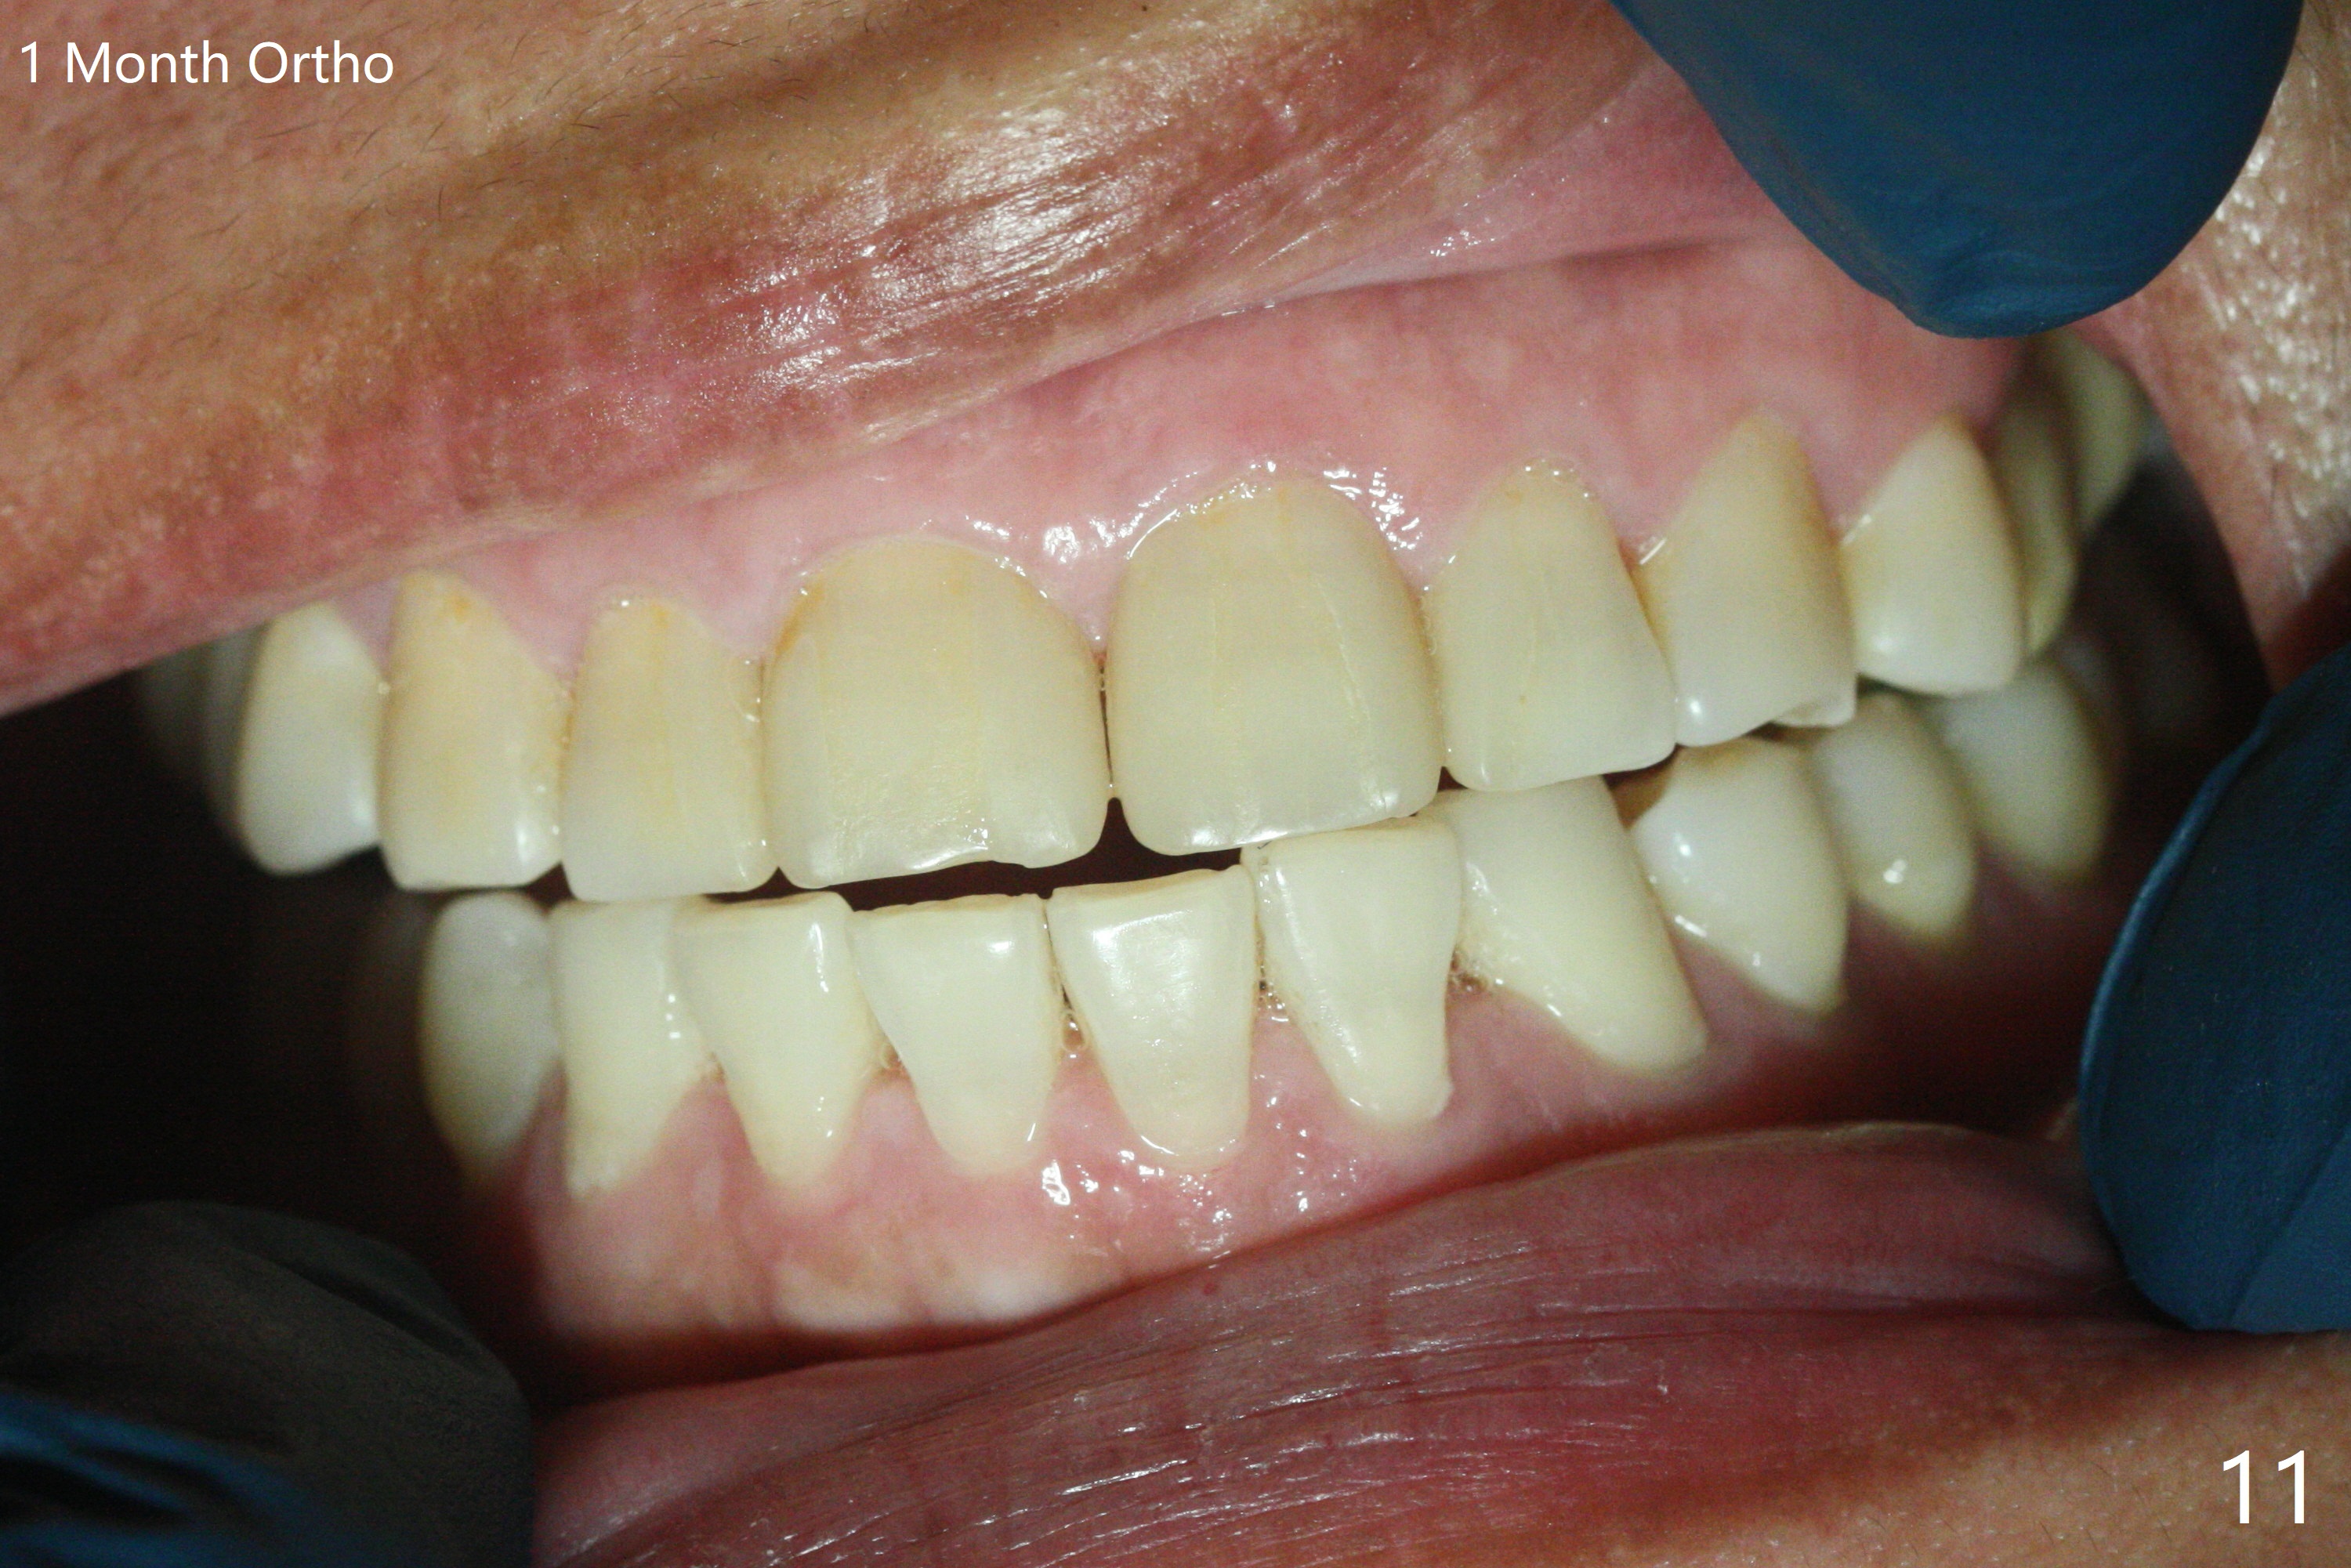

左上六植牙第三次失败后五个月,牙槽嵴宽度尚可,切开后放置导板,3.2乘19毫米园钻头好像接近上颌窦底板(图一),但是粘性骨块和4乘10毫米报废植体就不能进入上颌窦(图二),最后不得不使用3毫米Bicon骨凿,之后同一个报废植体就似乎进入上颌窦(图三),4.5乘8.5毫米正式植体植入深度和稳定性均正常(图四),腭侧植体稍微暴露,放置愈合螺丝后,放置骨粉和PRF膜,缝合,左上5植体放置5.7x4.5(4)毫米基台,固定牙周敷料。术后5.5个月植体好像整合(图五),缺牙间隙特别小,5临时牙冠(P)必须取出才能切开暴露植体,放置5.5x5毫米愈合基台(图六)。伤口愈合后,必须做渐进性负荷,之后做简单局部矫正,推7往远中,6缺失3年,7往近中倾斜移位。两周后牙周敷料脱落,伤口愈合,放置修复基台,故意将基台平面朝远中,足够空间制作临时牙冠(图七)。调整基台长度(比较图七,八)。制作连体牙冠(5,6),有意提高5牙冠高度,使左上7不与对合牙接触,有利于远中移位(图九)。也要在对侧提高咬合(图十)。局部矫正一个月后,磨去右侧咬合垫和磨短左上5,6临时牙冠,前牙还不能完全接触(图十一)。1-2星期前牙开合自行消失,取模做左上5,6牙冠。局部矫正似乎使左上7远中移位大约3毫米(比较图十二,十三)。粘固拧紧后(20 Ncm)14号牙牙冠咬合增高,拍摄根尖片(图十三),两个基台好像仍然完全就位,然后调整咬合。